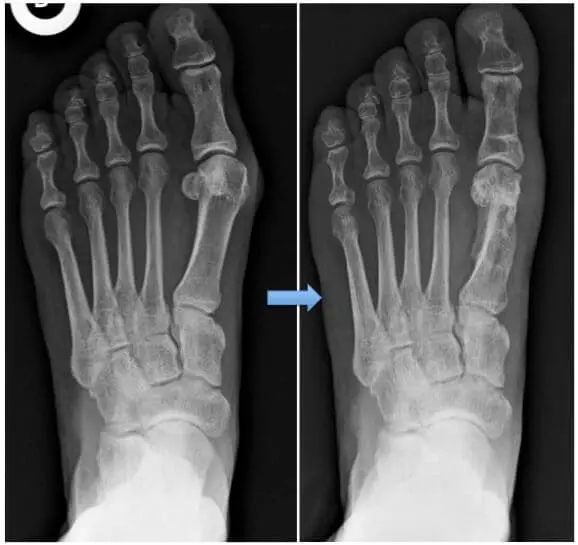

Certaines rares indications se voient proposées une indication de chirurgie percutanée, souvent fonction de l’expérience et de l’école du chirurgien.

La technique choisie dépendra de différents facteurs : la gravité et l’importance de la déformation, la possibilité de correction (c.-à-d. sa possibilité de réductibilité (remis en position droite par la pression des doigts), la mobilité comme la présence d’arthrose, la présence des pathologies associées comme la longueur du gros orteil par rapport aux autres, l’expérience du chirurgien… On cherchera toujours à corriger le déséquilibre articulaire en recentrant, entre autre, le métatarsien au-dessus des sésamoïdes. Différentes solutions sont brièvement résumées dont certaines sont communes: